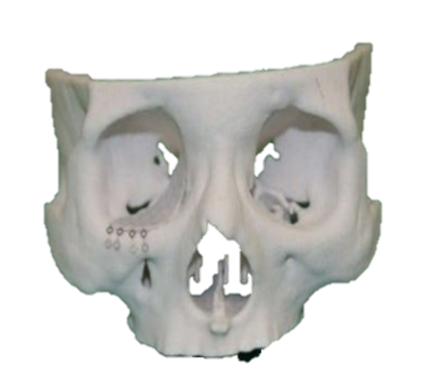

Cone Beam Computed Tomography (CBCT)

Special 3D imaging technique that provides detailed images of teeth, jaws, nerves, and surrounding structures. CBCT is quick, accurate, and offers 3 Dimensional knowledge compared to normal X-rays, ensuring better care for complex dental issues.